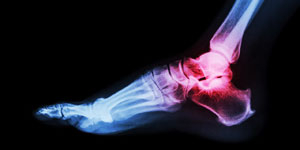

Bei der Gicht handelt es sich um eine Störung des Purinstoffwechsels. Infolge der hohen Harnsäure- konzentration im Blut kommt es zu Ablagerungen von Harnsäurekristallen in Gelenken und Geweben. Die Gicht zählt zu den typischen Wohlstandserkrankungen. Die Erkrankung ist seit dem 2. Weltkrieg zunehmend. Von dieser Krankheit sind mehr Männer als Frauen betroffen. Wobei deren Anteil nach den Wechseljahren steigt, was auf die hormonelle Umstellung zurückzuführen ist.